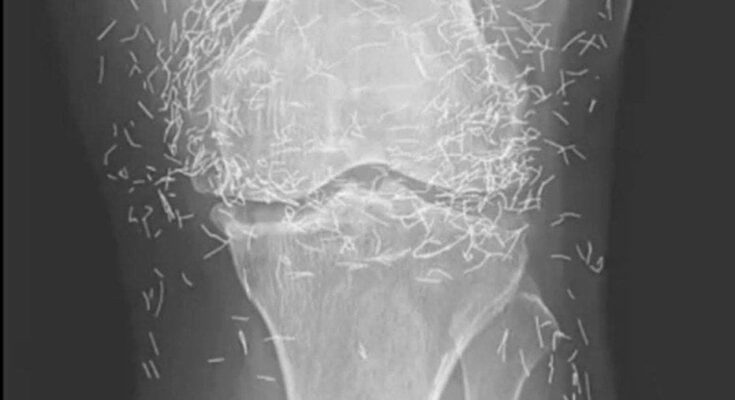

Years later, when doctors took X-rays to evaluate her knee condition, they weren’t prepared for what appeared on the images. Her knees were filled with dozens of bright, metallic flecks — tiny needles embedded deep within the joint area.

The findings were later documented in a case published by the New England Journal of Medicine.